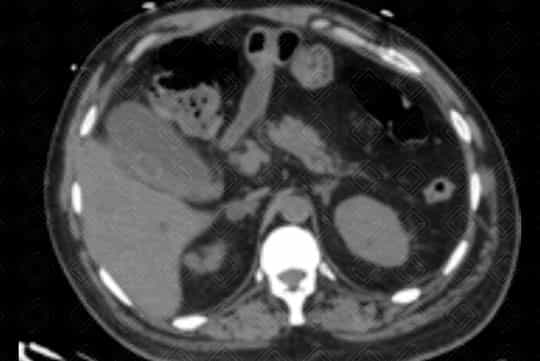

Descrição das figuras: Tomografia computadorizada de abdome com contraste venoso. Vesícula biliar contendo cálculo no seu interior, distendida, com espessamento parietal e densificação dos planos adiposos perivesiculares. Achados compatíveis com colecistite aguda.

• Tomografia computadorizada do abdome : Menos sensível quando comparado à ultrassonografia. Em alguns casos pode não visualizar o cálculo biliar. No entanto é excelente para a avaliação da inflamação perivesicular adjacente;